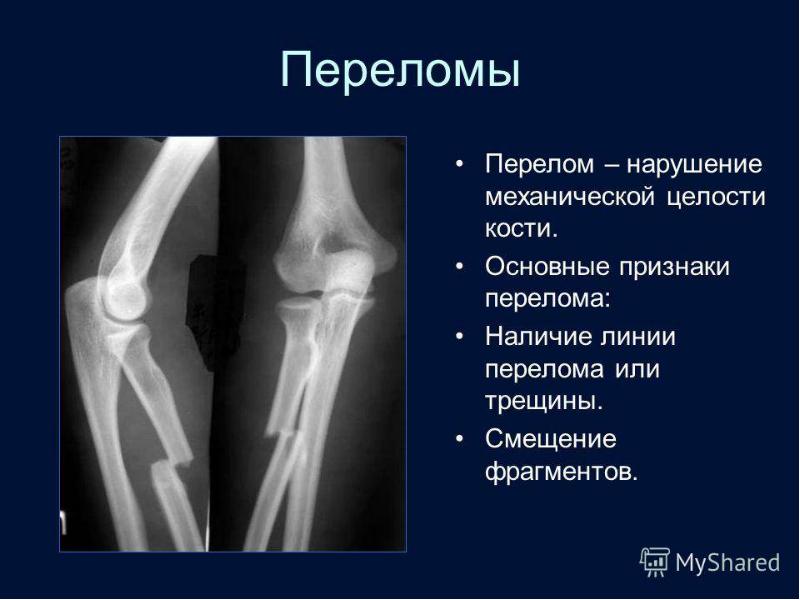

2 линий перелом